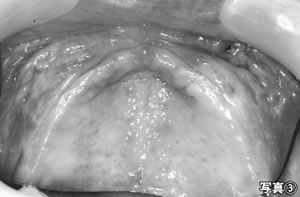

歯科では、不適合義歯を調整し、繊維腫の摘出と歯肉の形態修正手術を行いました(写真3)。その後、新しい義歯を製作しました。その結果、食事介助も円 滑になり、摂取量も増えました。アルブミン値も二・六(〇五年五月)から三・二(〇六年五月)に改善傾向が見えます。